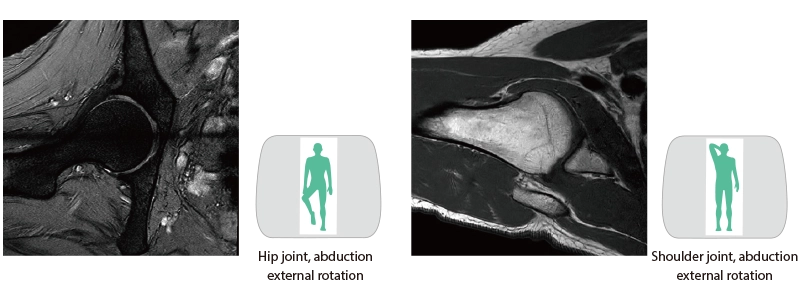

Wide bore and variety of coils to support comfortable examinations

The 70cm diameter wide bore improves comfort for patients. To match the wide bore, we also paid close attention to the size of the patient table to ensure a space of 62 cm for the moving part of the patient table. This allows for quick adaption to imaging in a variety of patient positions.

- * Not applicable to all body positions and patients.